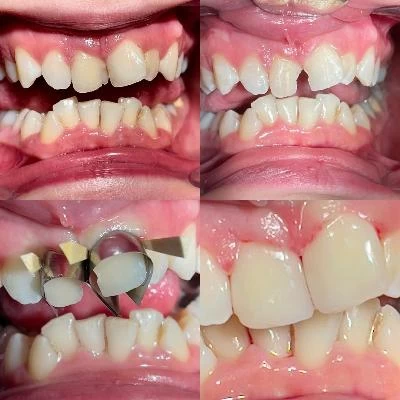

الدكتور فتح اله عباسپور طبيب أسنان

مجال النشاط الدكتور فتح اله عباسپور طبيب أسنان

• ترمیم دندان